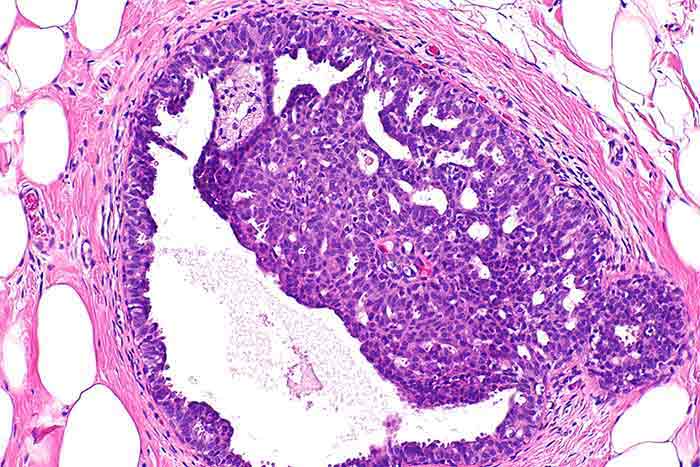

جهت تشخیص فیبروکیستیک سینه، پزشک علائم موجود را بررسی کرده و همچنین معاینه فیزیکی سینه ها را نیز انجام خواهد داد. فیبروکیستیک های سینه حالت، شکل و علائمی متفاوت با سرطان سینه دارند و پزشک با لمس سینه ها تا حد زیادی می تواند تفاوت آن ها را احساس کند. در صورتی که پزشک نیاز به اطلاعات بیشتر جهت تشخیص دقیق تر داشته باشد، بیمار باید ماموگرافی یا سونوگرافی سینه انجام دهد. در انتها برای اطمینان و تشخیص نهایی، ممکن است پزشک درخواست بیوپسی سینه را دهد.

کیست ساده سینه؛ آنها کیستهایی هستند که ساختار مایع در آنها یکسان است، اطراف آن صاف است، ساختار عروقی وجود ندارد و احتمال تبدیل آنها به سرطان وجود ندارد. کیست پیچیده سینه که از ترکیب چند کیست ایجاد میشود، کیست سینه با محتوای متراکم زمانی که مایع درون کیست بیش از حد متراکم باشد، نامیده میشود. کیست سینه با ساختار داخلی نامنظم دارای خونریزی یا باقی مانده بافت در کیست پستان میباشد.

مرجعترین روش تشخیصی تصویربرداری اولتراسوند است. پس از این روش، مایع کیست با ورود به کیست از طریق انژکتور تحت هدایت سونوگرافی تخلیه میشود. برخی از کیستها ممکن است با این فرآیند ترشح به طور کامل ناپدید شوند. نمونه مایع و بافت گرفته شده به پاتولوژی فرستاده میشود. درمان با توجه به نتیجه تعیین میشود.